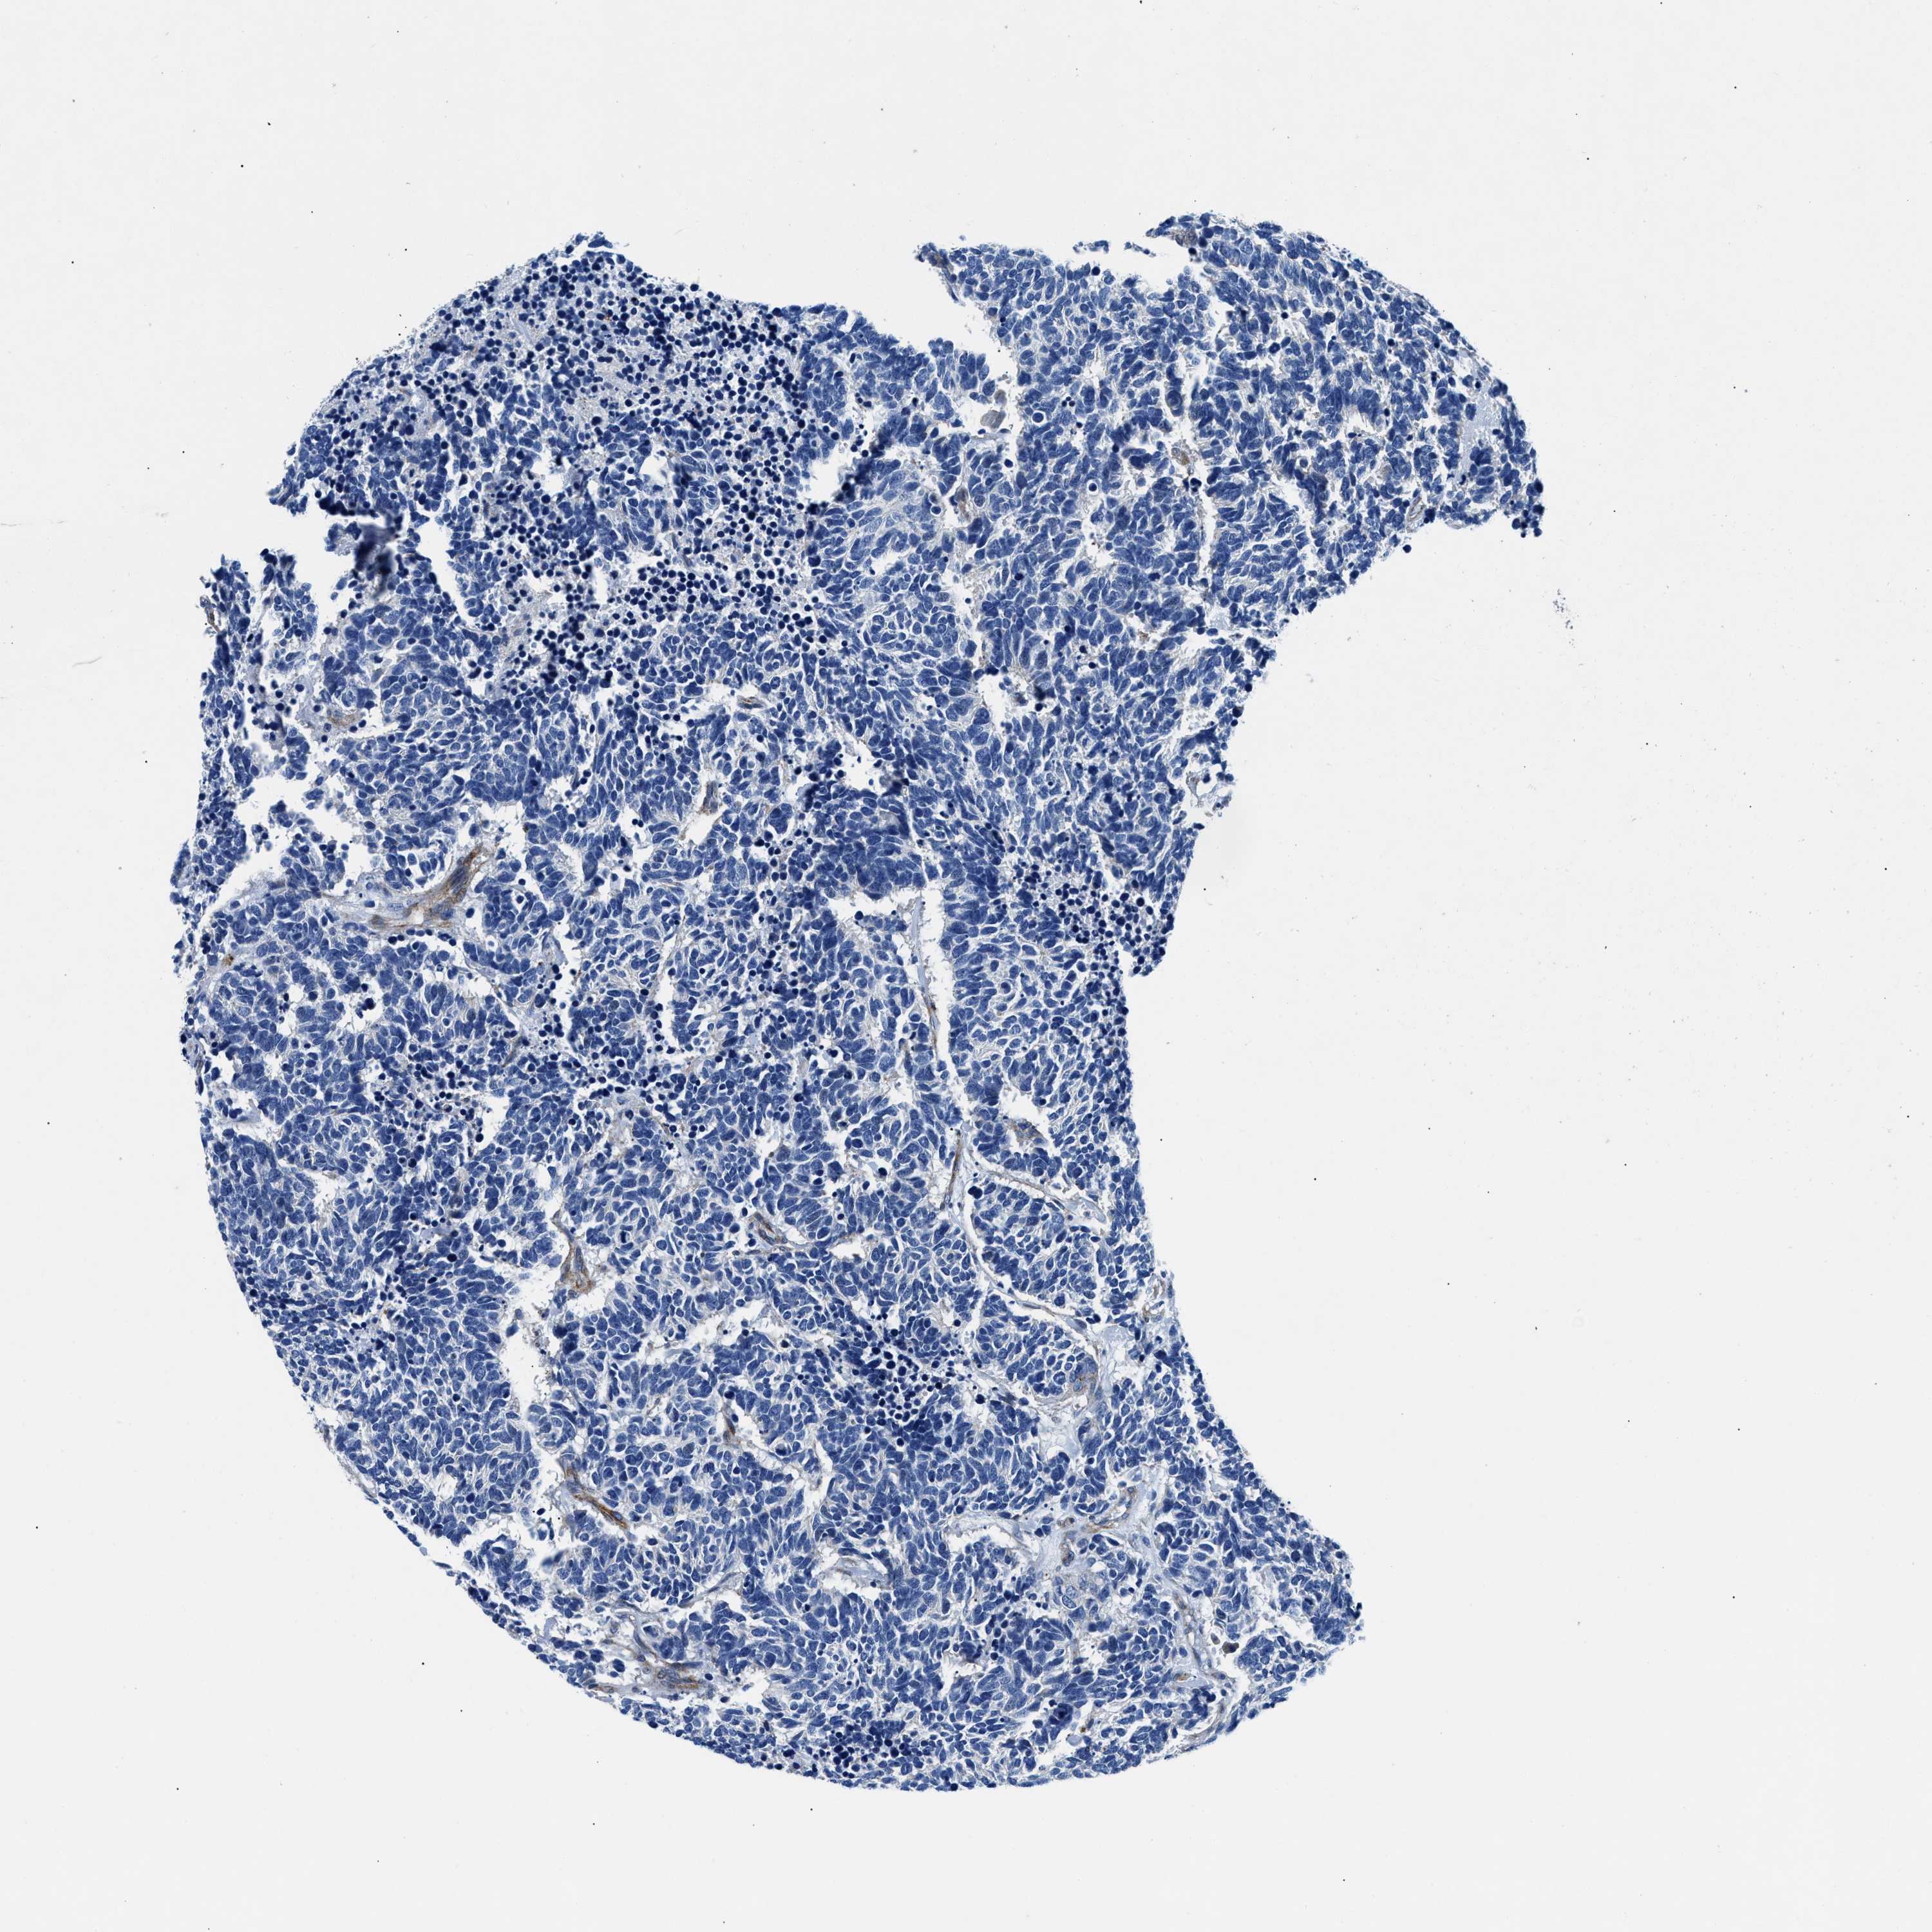

CARCINOID - Protein expressioni

A mouse-over function shows sample information and annotation data. Click on an image to view it in a full screen mode. Samples can be filtered based on level of antibody staining by selecting one or several of the following categories: high, medium, low and not detected. The assay and annotation is described here.

Antibody stainingi

Antibody staining in the annotated cell types in the current human tissue is reported as not detected, low, medium, or high, based on conventional immunohistochemistry profiling in selected tissues. This score is based on the combination of the staining intensity and fraction of stained cells.

Each image is clickable and will lead to virtual microscopy that enables deeper exploration of all samples and also displays staining intensity scores, fraction scores and subcellular localization as well as patient and tissue information for each sample.

Antibody CAB001960

Antibody CAB016353

Staining

High

Medium

Low

Not detected

Intensity

Strong

Moderate

Weak

Negative

Quantity

>75%

75%-25%

<25%

None

Location

Nuclear

Cytoplasmic/membranous

Cytoplasmic/membranous,nuclear

Carcinoid, malignant, NOS

Carcinoma, NOS